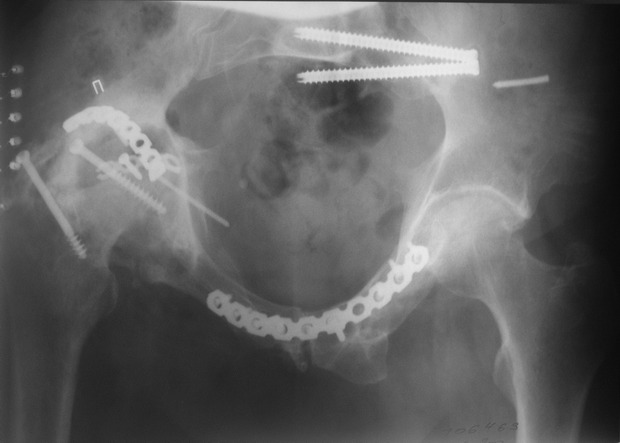

Пациент 49 лет, паровозная травма 23.2.2006, получил вертикальная нестабильное повреждение таза, разрыв левого крестцово-подвздошного сочленения, перелом лонной, седалищной костей слева, T-образный оскольчатый перелом правой вертлужной впадины с переломом заднего края, вывих правого бедра, посттравматическая пояснично-крестцовая плексопатия с обеих сторон, паралич мышц правой голени. В день травмы - вправление вывиха, скелетное вытяжение, 14.3.2006 чрескостный остеосинтез таза. 20.4.2006 остеосинтез правой вертлужной впадины пластинами, осложнившийся нагноением межмышечной гематомы правой ягодичной области. Получал консервативное лечение, было достигнуто полное заживление раны. 24.7.2006 введены илиосакральные винты слева. С декабря 2006 года и по настоящее время ходит на костылях без опоры на правую ногу. Планируется THA. Помогите определиться с вариантом костной пластики? И какую укрепляющую конструкцию использовать?

Мне кажется, будет вполне достаточно кольца Muller, костная пластика из остатков головки чипсами (нужно иметь виду, что собственной головки может не хватить и она может оказаться ненадлежащего качества, поэтому лучше иметь запас аллокости) возможна и структурная пластика, точно алло.

Бесцементная чаша, с восстановлением нормального центра вращения и с костной аутопластикой дна впадины. А Рыков Хабаровск.

Паровозы-элктровозы. Суть не в этом. Сейчас - аутокостная реконструкция вертлужной впадины. Ало - оногда секвестрация. Не надо риска. И, есле готовы технически, эндопротезирование. Лучше бесцесентная чашка прес-фит (допустем - зимет) с дополнительной фиксацией винтами. Возможен вариант кольца Мюллеа. Операцию возможно выполнить в один либо два этапа. Первы -реконструкция вертлужной впадины,а второй - протез через 3-4 мес. Кость лучше брать из гребня, т.к. головка с некрозом-склерозом-фиброзом.